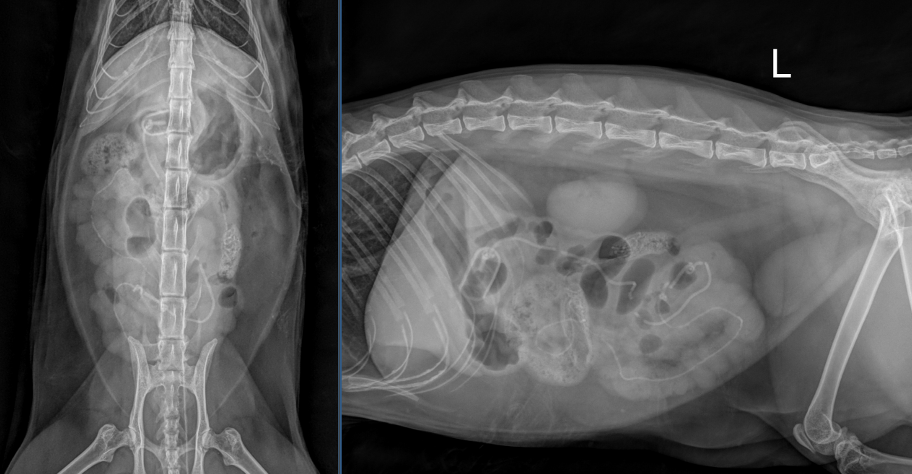

Liebe Kolleg:innen, vielen Dank für das Zusenden der Röntgenaufnahmen der Katze Bonita. In den vorliegenden dextro-sinistralen sowie ventro-dorsalen abdominalen Röntgenbildern zeigen sich mehrere auffällige Veränderungen im Bereich des Magen-Darm-Trakts. Auf Höhe des Übergangs von Pylorus zu proximalen Duodenum ist eine ovoide Struktur mit mineraldichtem peripherem Saum erkennbar, die zu einer mechanischen luminalen Einengung in diesem Bereich führt (erste grün gepunktete Kreise). Ausgehend von dieser Struktur projiziert sich ein lineares, röntgendichtes Material innerhalb des gesamten Dünndarms, wodurch es zu einer markanten Auffädelung mehrerer jejunaler Darmabschnitte kommt (grüne Pfeilköpfe). Eine weitere ähnlich ovale röntgendichte Struktur befindet sich innerhalb des Jejunums, die eine zusätzliche mechanische Obstruktion verursacht (zweite grün gepunktete Kreise). Es bestehen innerhalb des gastrointestinalen Trakts multifokale Gasblasen, die von weichteildichtem Darminhalt umgeben sind. Das fadenförmige Fremdmaterial endet auf Höhe des Colon descendens in einer kotähnlichen Formation (pinker Pfeilkopf). Aborad dieser Struktur stellt sich das restliche Colon leer dar.

Der Magen ist zusätzlich leicht bis moderat Gas gefüllt. Es besteht kein Hinweis auf freie Flüssigkeit oder freies Gas innerhalb der Peritonealhöhle. Die Leber stellt sich spitzrandig und gut abgrenzbar dar. Milz, Nieren sowie die Harnblase sind ohne besonderen Befund. Im ventralen Anteil des Abdomens ist in der seitlichen Projektion ein Artefakt erkennbar, sehr wahrscheinlich bedingt durch Ultraschallgel des zuvor durchgeführten A-FASTs (grüner gepunkteter Quadrant), welches somit als nicht pathologisch zu bewerten ist. Zudem besteht intraabdominal ein deutlicher Anteil an fettdichter Verschattung. Der abgebildete Bewegungsapparat ist unauffällig.

Zusammenfassend ist von einem mechanischen Ileus auszugehen, verursacht durch röntgendichtes Fremdmaterial im Bereich des Pylorus/proximalen Duodenums sowie des Jejunums. Zusätzlich befindet sich ein linearer Fremdkörper innerhalb des Dünndarms, der zu einer Auffädelung multipler Dünndarmschlingen führt, derzeitig ohne Hinweis auf Perforation. Es besteht jedoch ein erhebliches Risiko für Strangulation, Ischämie und Darmperforation, womit es sich hierbei um einen chirurgischen Notfall handelt und dringend zu einer zeitnahen operativen Versorgung geraten wird.